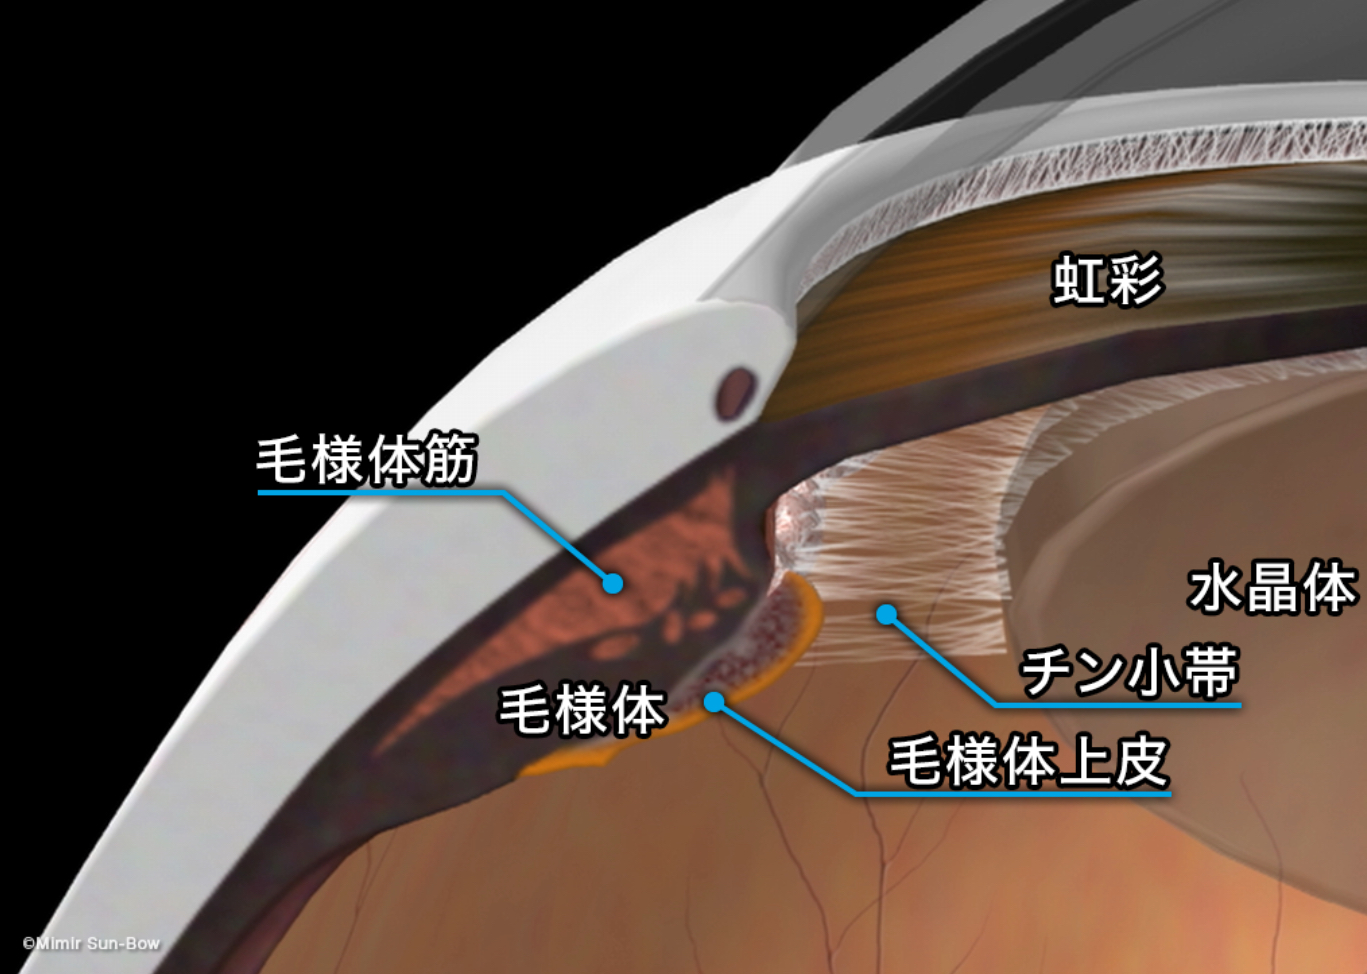

炎症が強かった上で手術した影響で、おそらく、毛様体という組織(眼の中の水を作る働きがある)の機能が低下し、眼圧が低く、眼の張りが弱く、脈絡膜剥離と低眼圧黄斑症という状態を起こしていますが、炎症の原因は取れていると思うので、少しずつ毛様体の機能が戻り状態が改善してくるのを待ちたいと思います。

↑毛様体で眼の中の水(房水)が産生されます。